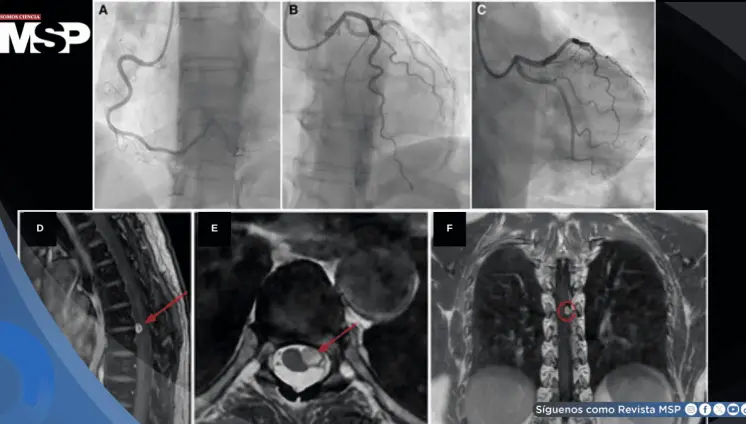

Reportan el aneurisma aórtico sifilítico más grande en décadas en paciente de 59 años

Febrero 05, 2026